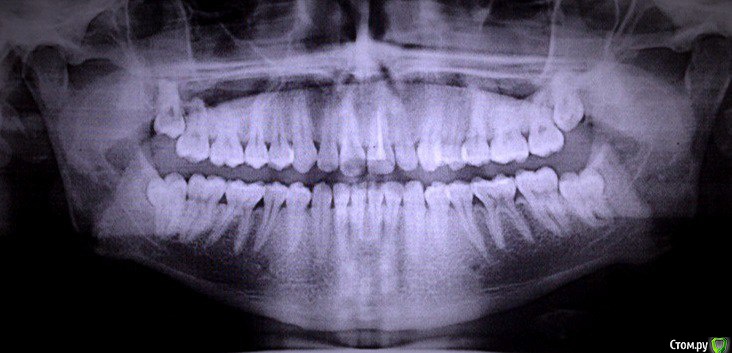

ufa777vanya Опубликовано 3 января, 2016 Поделиться Опубликовано 3 января, 2016 Беспокоит искривление передних зубов как нч, так и верхней. пока режется только нижний левый на снимке, по факту он справа получается. Удалять ли мне их или нет? Ссылка на комментарий

AlexanderGudkov Опубликовано 3 января, 2016 Поделиться Опубликовано 3 января, 2016 Удалить все восьмерки 2 Ссылка на комментарий

red_butler Опубликовано 3 января, 2016 Поделиться Опубликовано 3 января, 2016 +1 все мудрые зубы удалять 1 Ссылка на комментарий

AlexanderGudkov Опубликовано 3 января, 2016 Поделиться Опубликовано 3 января, 2016 а с чем это связано, можете вкратце объяснить, если не сложно?Недостаток места в зубных рядах для восьмерок. Они, в попытке встать на место, толкают все зубы и это приводит к "искривению" зубов передних) Надо удалить их и ортодонтию) 2 Ссылка на комментарий

brg Опубликовано 3 января, 2016 Поделиться Опубликовано 3 января, 2016 Зубы мудрости до армии удалите (все 4 штуки) Ссылка на комментарий